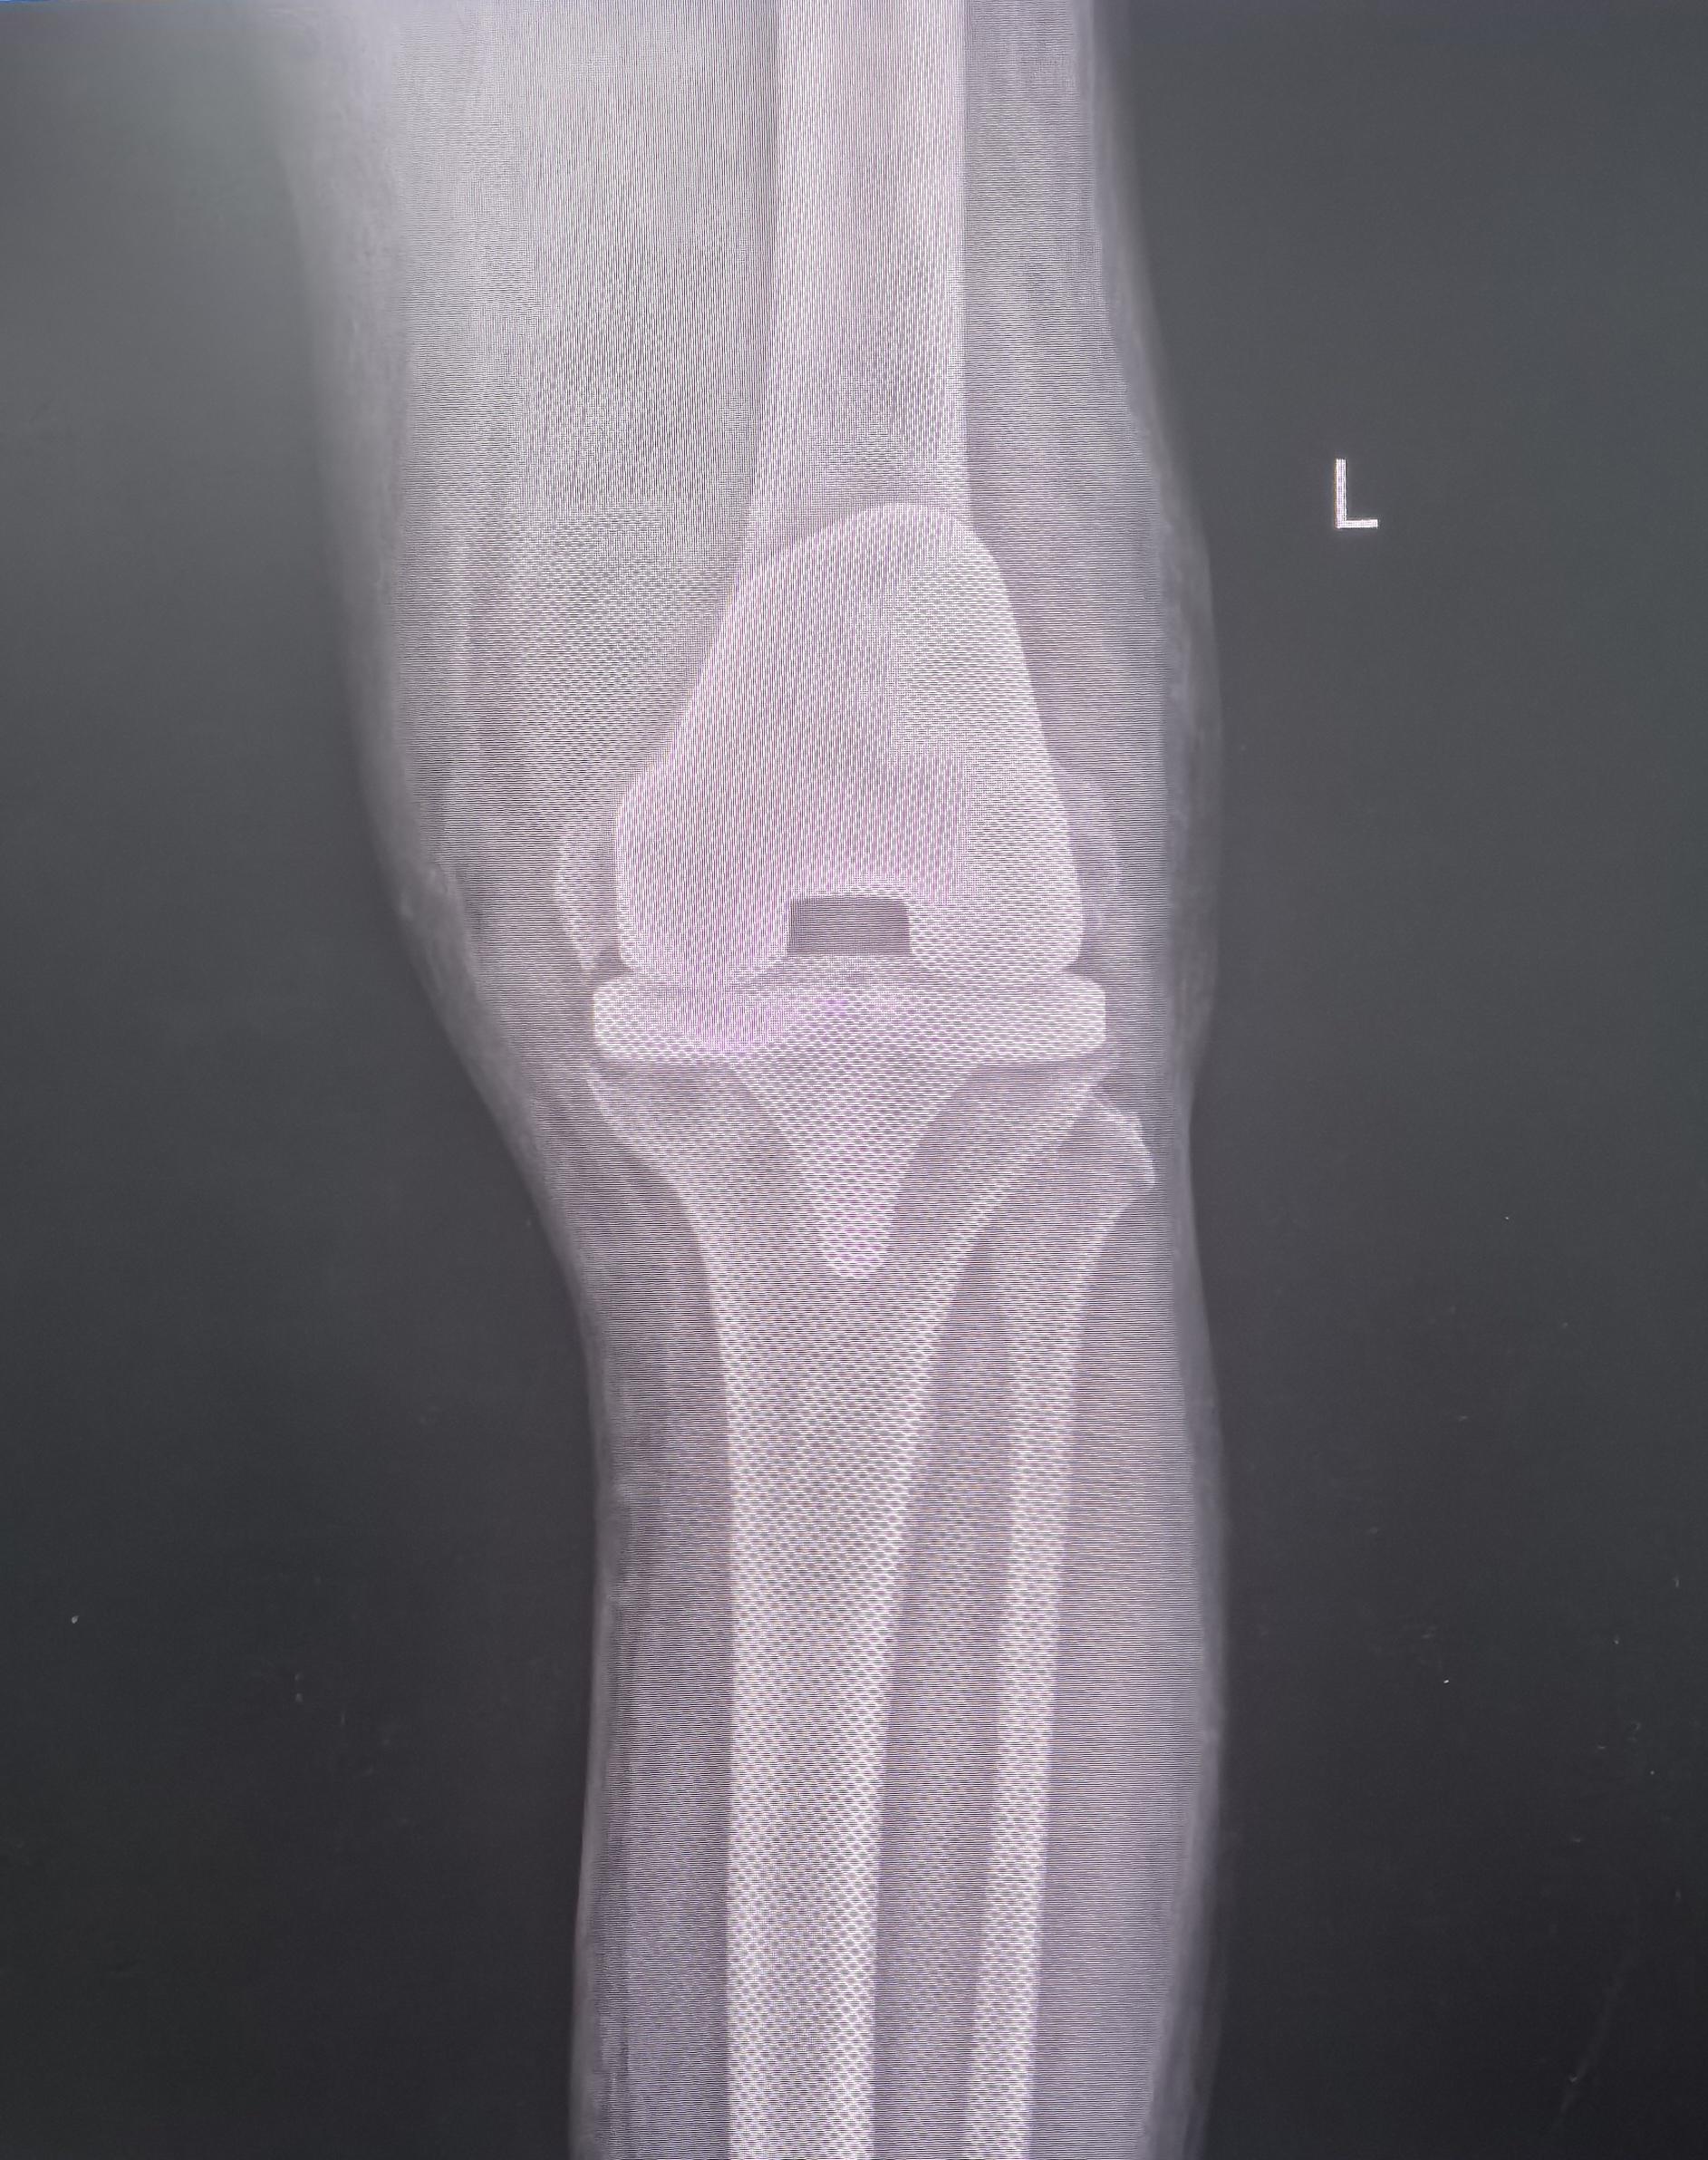

膝关节翻修。80岁老爷子,膝关节置换术后假体松动,一期翻修,再次续命20年🌹